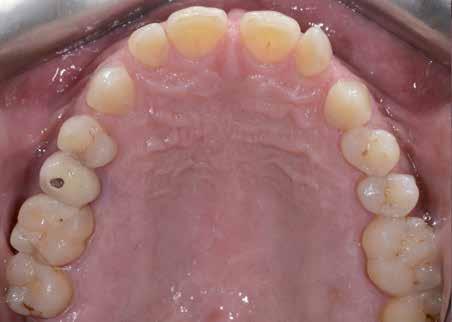

Hölgy páciensem az első konzultáció során tipikus kórtörténetet vázolt fel: Gyermekkora óta szeretett volna fogszabályozó készüléket, hiszen mindig is zavarta a class 2-es eltérésnél tipikusan jellemző nagy overjet (1-3. képek), és természetesen az ezáltal kifelé álló felső metszőfogai, részben a felső metszők protrúziója, részben pedig a disztálisan elhelyezkedő mandibula miatt. Annak ellenére, hogy több fogszabályozó szakorvosnál is járt az évek során, de mivel saggitális eltérése és az alsó metszőfogak torlódása miatt négy kisőrlőfog extrakcióját, illetve emellett sokszor állcsont műtétet is javasoltak neki, nem vágott bele a kezelésbe (4-5. képek).

A konzultáció során arról is beszéltünk – ahogy az ilyenkor lenni szokott –, sohasem szeretett igazán mosolyogni, de a Pitts Protokolloknak köszönhetően az arc- és mosolyesztétikai céloknak megfelelően kerül megvalósításra az okklúziós korrekció. Az okklúziós kezelési célok az alábbiak voltak: a felső és alsó fogív nivellálása és tágítása, az alsó fogsor/ mandibula mezializálása, valamint a harapás megemelése által a mélyharapás rendezése.

Az esztétikai kezelési céloknál a Pitts elvek szerint a legfontosabb fogak a felső, középső metszők, a cél ezeknek a tökéletes pozícióba állítása. A legfontosabb, hogy a felső, középső metszők labiális felszíne merőleges legyen a Frankfurti Horizontálisra, vagyis természetes fejtartásnál (Natural Head Position) párhuzamos legyen a vertikális síkkal (6. kép) Ehhez az ideális pozícióhoz képest minél protrudáltabbak a felső metszők, annál laposabb, szemből nézve kevésbé ívesebb lesz a mosolyvonal, másrészt optikailag a metszők

hossza is rövidül, azaz a Vertical Incisor Display (Metszőfog láthatóság) csökken. A miniesztétikai, vagyis a mosolyesztétikai eredmény szempontjából egyik jelenség sem kívánatos. A mikroesztétika (a fog- és ínyesztétika) is szorosan hozzátartozik az esztétikai paraméterekhez, ennek tökéletesítése is minden esetben a célok közé tartozik fogkontúrálással vagy esztétikai fogászati felépítéssel, továbbá interproximális redukcióval és szükség esetén lézeres ínykontúrálással (7. kép).

A fogkontúrálás és az interproximális redukció alkalmazásával a mikroesztétikai részletek tökéletesítése is megtörtént (11. kép) A kezelés mindössze 16 hónapig tartott, megtörtént a rágófunkció helyreállítása, és az esztétikai végeredmény sokéves várakozás után valóban fordulópontot jelentett páciensünk életében (12-14. képek).